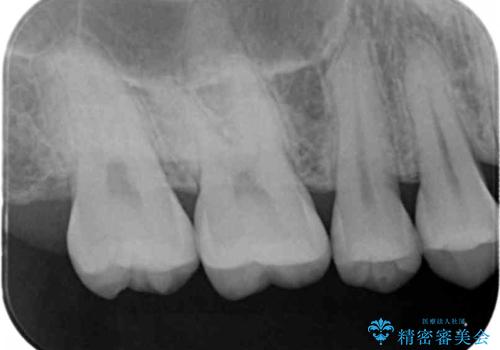

- 銀歯を白くしたいとのことで来院されました。

セラミックインレーでの治療をしていきます。

銀歯をセラミックにやり替えることで審美性を改善することができます。

適合の良いセラミックインレーを装着することで、今後の虫歯発生リスクを抑えることができます。